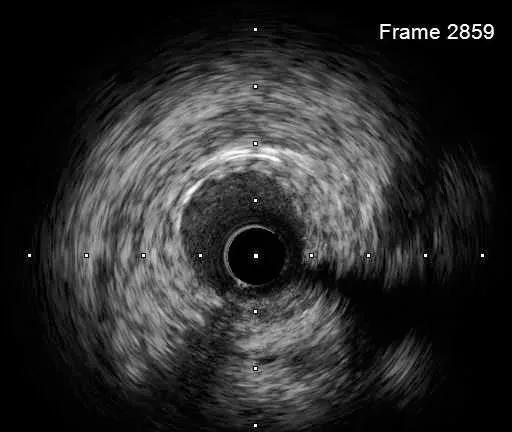

DEB bingo 2.5*30mm 10atm 结果满意

IVUS-3